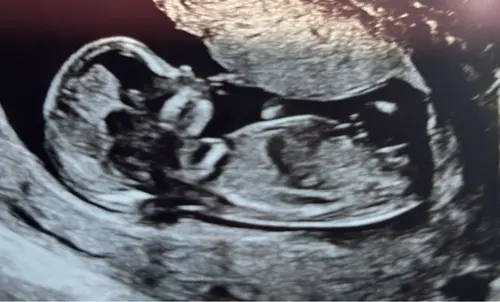

Dan gaan we hier verder 馃槂 wat denken jullie aan de Skull te zien, jongen/meisje ?馃挋馃┓

Dan gaan we hier verder 馃槂 wat denken jullie aan de Skull te zien, jongen/m ...